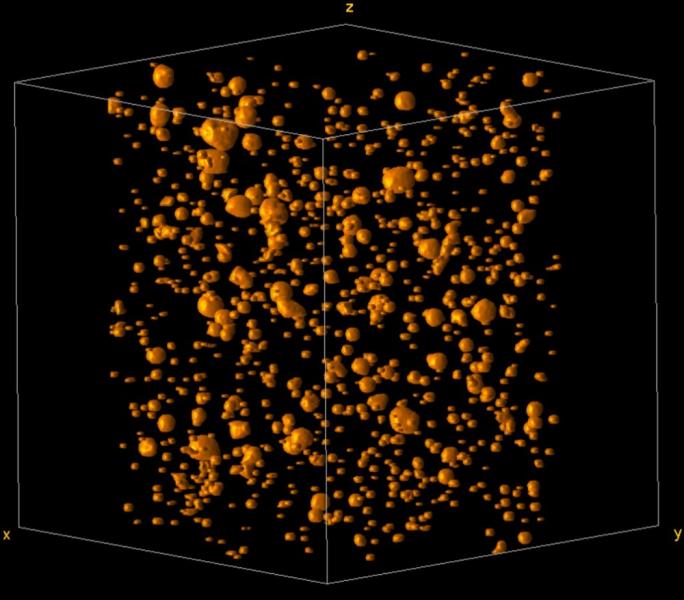

Representación esquemática de la redistribución celular en la sangre y el pulmón de pacientes COVID-19 con diversos grados de severidad / UAM